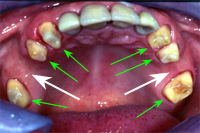

Ein 32 Jahre alter Mann kommt im November 1984 mit Zahnweh am unteren linken, zweithintersten Molaren (Backenzahn) in die Praxis. Das Röntgenbild von Abb. 1 zeigt insuffiziente Wurzelfüllungen bei allen drei Wurzelkanälen und an den Wurzelspitzen sogenannte Granulome, sichtbar als schwarze Flecken (grüne Pfeile in Abb. 1).

In Abb. 2 ist das Röntgenbild 22 Jahre nach korrekter Wurzelbehandlung mit dem nun überkronten Zahn zu sehen. Der Knochen um die Wurzelspitzen ist entzündungsfrei gesund.